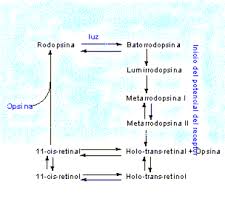

365 × 364 - gimolimpo.com

{"cb":18,"cl":3,"ct":3,"id":"RByD-gWPl1RUPM:","isu":"gimolimpo.com","itg":0,"ity":"gif","oh":364,"ou":"http://www.gimolimpo.com/Paginas/vitamina%20A_archivos/image005.gif","ow":365,"pt":"La

vitamina A tiene dos fuentes naturales: el retinol, procedente

...","rid":"V-3-RI0JmuC_QM","rmt":0,"rt":0,"ru":"http://www.gimolimpo.com/Paginas/vitamina%20A.htm","s":"Síntesis

rodopsina","sc":1,"th":224,"tu":"https://encrypted-tbn0.gstatic.com/images?q\u003dtbn:ANd9GcTCtG14SPsmaSgrb9w8d80Q4gBRtpNxYVgEPB6fflgdyK9G32sj0Q","tw":225}